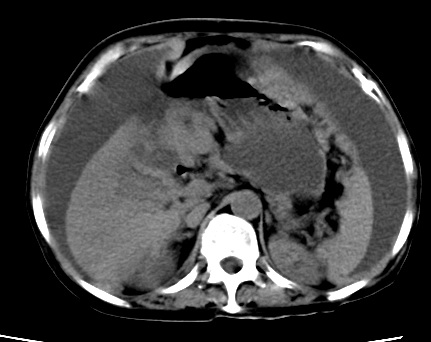

既往5年前卵巢癌行子宫及附件切除,右乳癌术后一年,考虑腹膜转移?

大量腹水,考虑腹膜转移。肝脏低密度灶。1囊肿,2转移。

1)结合病史,考虑腹膜及网膜转移瘤。2)肝脏多发性低密度灶,不排除转移瘤。3)大量腹水。

考虑卵巢癌行子宫术后复发,并肝、腹腔 、大网膜转移可能性大。

大量腹水。